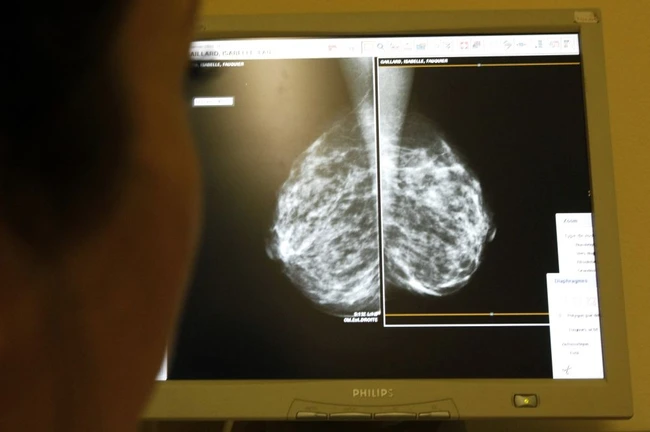

Prea puţine românce îşi fac mamografii pentru a depista timpuriu cancerul de sân FOTO Adevărul

Femeile trecute de 40 de ani ar trebui să-şi facă în mod regulat mamografii astfel încât să depisteze timpuriu afecţiuni precum cancerul de sân, patologie tot mai frecventă în ultimii ani. Doar în România, 10.000 de femei sunt diagnosticate cu această boală.

Diagnosticul şi tratamentul se pot pune în urma autopalpării, în urma screeningului mamografic. Cel din urmă scade cu 40% incidenţa bolii. Pentru stadiul I al bolii se folosesc tratamente agresive cu rol curativ, iar în stadiul IV se folosesc tratamente blânde, concepute pentru a creşte calitatea vieţii.